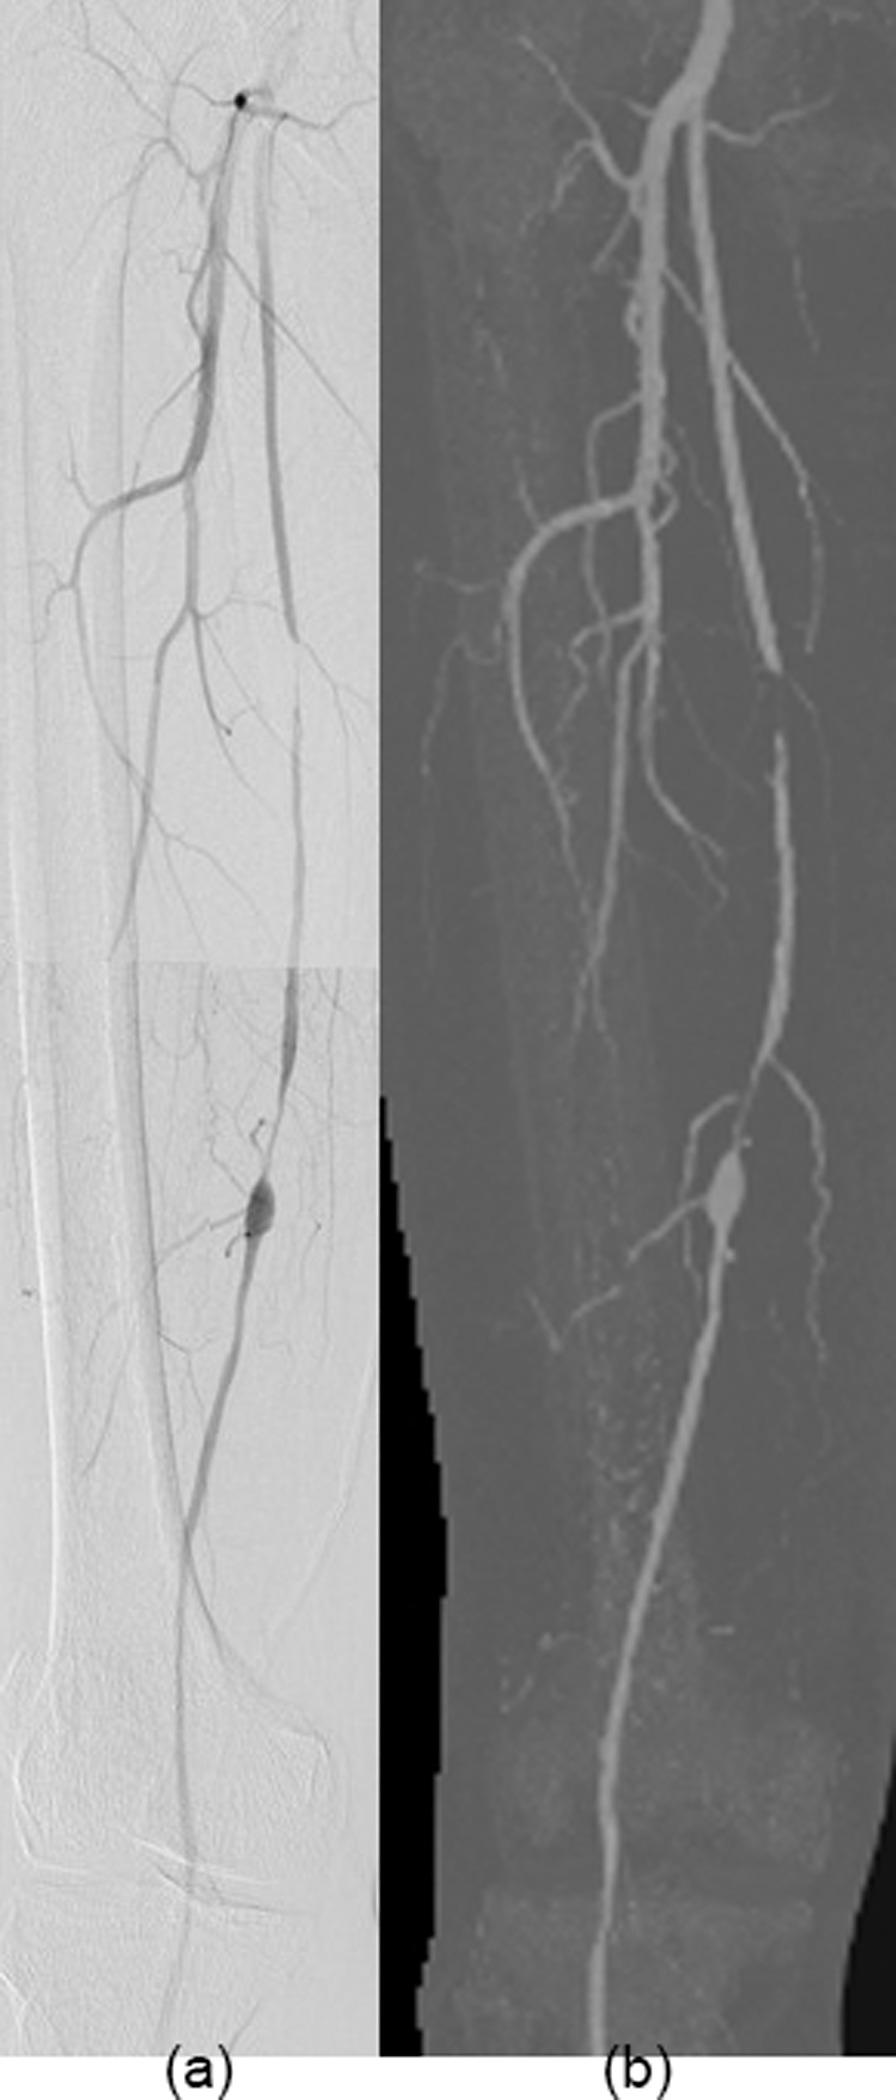

To evaluate the image quality of lower extremity computed tomography angiography (CTA) with deep learning-based reconstruction (DLR) compared to model-based iterative reconstruction (MBIR), hybrid-iterative reconstruction (HIR), and filtered back projection (FBP).

Fifty patients (38 males, average age 59.8 ± 19.2 years) who underwent lower extremity CTA between January and May 2021 were included. Images were reconstructed with DLR, MBIR, HIR, and FBP. The standard deviation (SD), contrast-to-noise ratio (CNR), signal-to-noise ratio (SNR), noise power spectrum (NPS) curves, and the blur effect, were calculated. The subjective image quality was independently evaluated by two radiologists. The diagnostic accuracy of DLR, MBIR, HIR, and FBP reconstruction algorithms was calculated.

The CNR and SNR were significantly higher in DLR images than in the other three reconstruction algorithms, and the SD was significantly lower in DLR images of the soft tissues. The noise magnitude was the lowest with DLR. The NPS average spatial frequency (f) values were higher using DLR than HIR. For blur effect evaluation, DLR and FBP were similar for soft tissues and the popliteal artery, which was better than HIR and worse than MBIR. In the aorta and femoral arteries, the blur effect of DLR was worse than MBIR and FBP and better than HIR. The subjective image quality score of DLR was the highest. The sensitivity and specificity of the lower extremity CTA with DLR were the highest in the four reconstruction algorithms with 98.4% and 97.2%, respectively.

Compared to the other three reconstruction algorithms, DLR showed better objective and subjective image quality. The blur effect of the DLR was better than that of the HIR. The diagnostic accuracy of lower extremity CTA with DLR was the best among the four reconstruction algorithms.